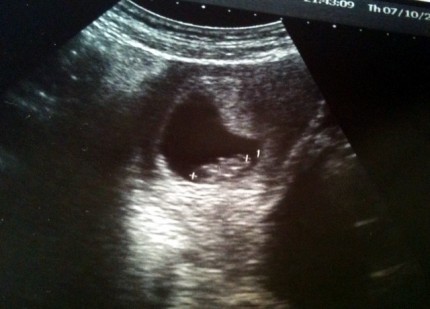

Při registraci se udělal kontrolní ultrazvuk, u kterého už jsme byli oba. Jedině dobře, protože Ivan má na ty tvary fakt o mnoho lepší oko než já! Ale slyšeli jsme přes břicho bouchat srdíčko, to bylo fajn. Mini mimi mělo 19 milimetrů a už celkem zřetelnou tu hlavičku… Takovou… velikou, že?